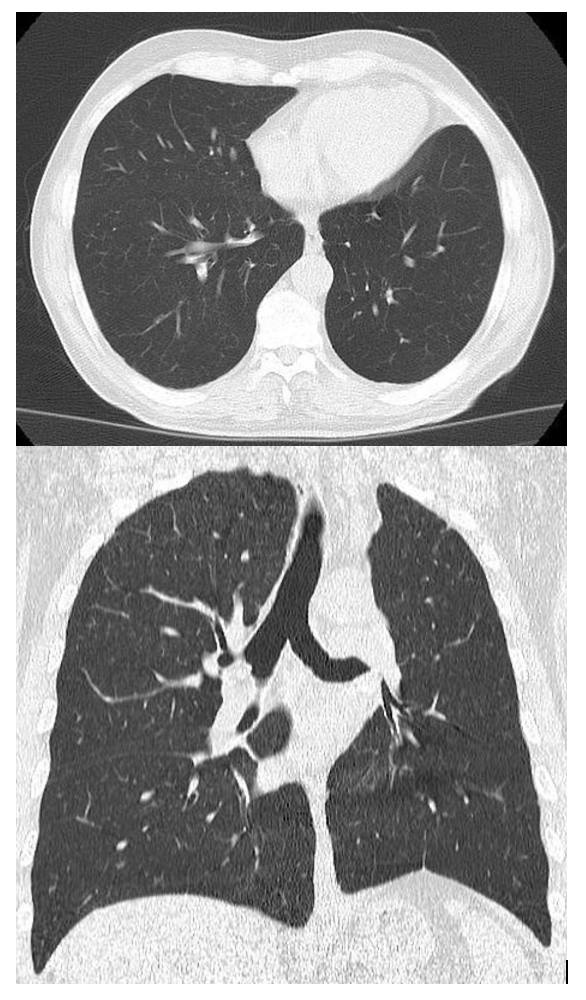

10

What are the features of RML collapse on CT scan

CT features: (4)

Triangular opacification abutting R heartborder, thinner at the hilum in axial image

Horizonal fissure rotates anteromedially

Oblique feature bows anteriorly

RUL rotates anterolaterally and RLL rotates posterolaterally and meets lateral to the collapsed RML